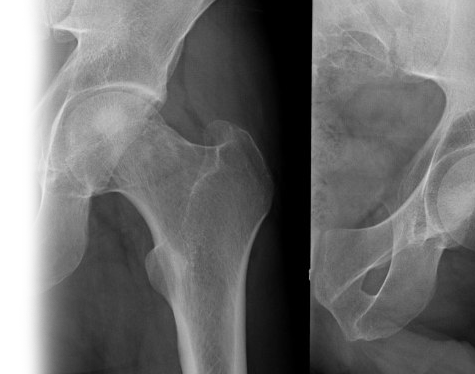

Рентгенография тазобедренного сустава – важный метод прицельного исследования, который позволяет оценить состояние тазобедренного сустава. Диагностическая услуга выполняется в двух проекциях.

Рентген позволяет исключить патологию тазобедренного сустава костно-травматического, дегенеративно-дистрофического, опухолевого генеза.